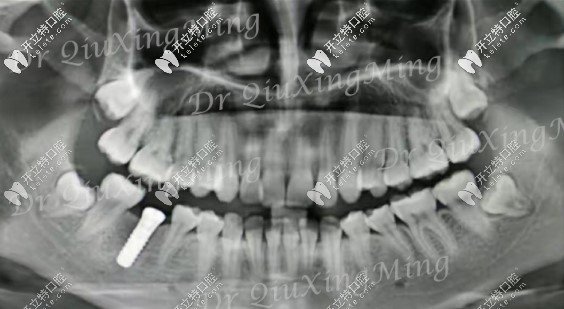

朋友的牙片▼

第1磨牙缺失幾年后的ct

第1磨牙缺失種植后的圖片